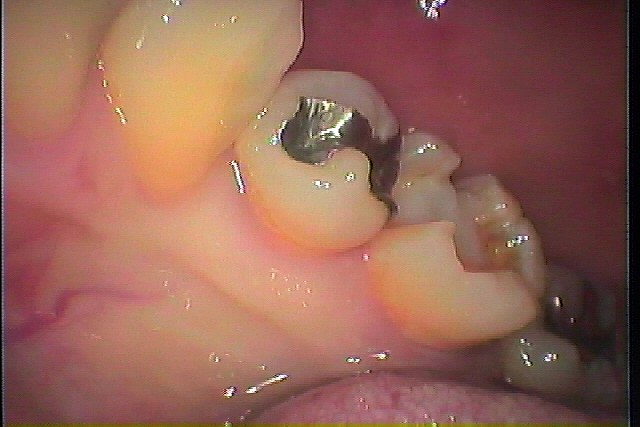

銀歯が外れた診てほしい 銀歯の下は大きく虫歯になっていることが多いです|お知らせ |広島市安佐南区の歯科医院 銀歯が外れた診てほしい 銀歯の下は大きく虫歯になっていることが多いです トップ お知らせ・ブログ お知らせ 銀歯が外れた診てほしい 銀歯の下は大きく虫歯になっていることが多いです 銀歯が外れた診てほしい 銀歯の下は大きく虫歯になっていることが多いです 銀歯が外れたところになります 中は黒く大きく虫歯になっていました レントゲンになります 虫歯を除去していきます 隣接に及ぶ虫歯が存在していました CR樹脂にて覆罩しています セラミックにてきれいに修復しています 左上5番 銀歯が外れた 隣接部には虫歯が存在していました 虫歯を除去していきます セレックセラミックにて審美的に修復しています Web診療予約 初めての方へ 選ばれ続ける理由 院内設備について 歯が痛いしみる一般歯科 歯がぐらぐらする歯周病 健康な歯を保ちたい予防歯科 子供の虫歯予防をしたい小児歯科 銀歯をセラミックに審美歯科 白い歯を目指しませんか?ホワイトニング 矯正専門医がいるので安心矯正歯科 抜けた歯を補いたいインプラント・入れ歯 医院案内 スタッフ紹介 メリィハウス歯科クリニックオフィシャルホームページ ラベンダー歯科クリニックオフィシャルホームページ お知らせ・ブログ ホーム 診療科目 一般歯科 歯周病治療 予防治療 小児歯科 審美治療 ホワイトニング 矯正歯科 入れ歯・インプラント マウスピース矯正 初めての方へ 院長・スタッフ 設備紹介 医院案内・アクセス メニューを閉じる